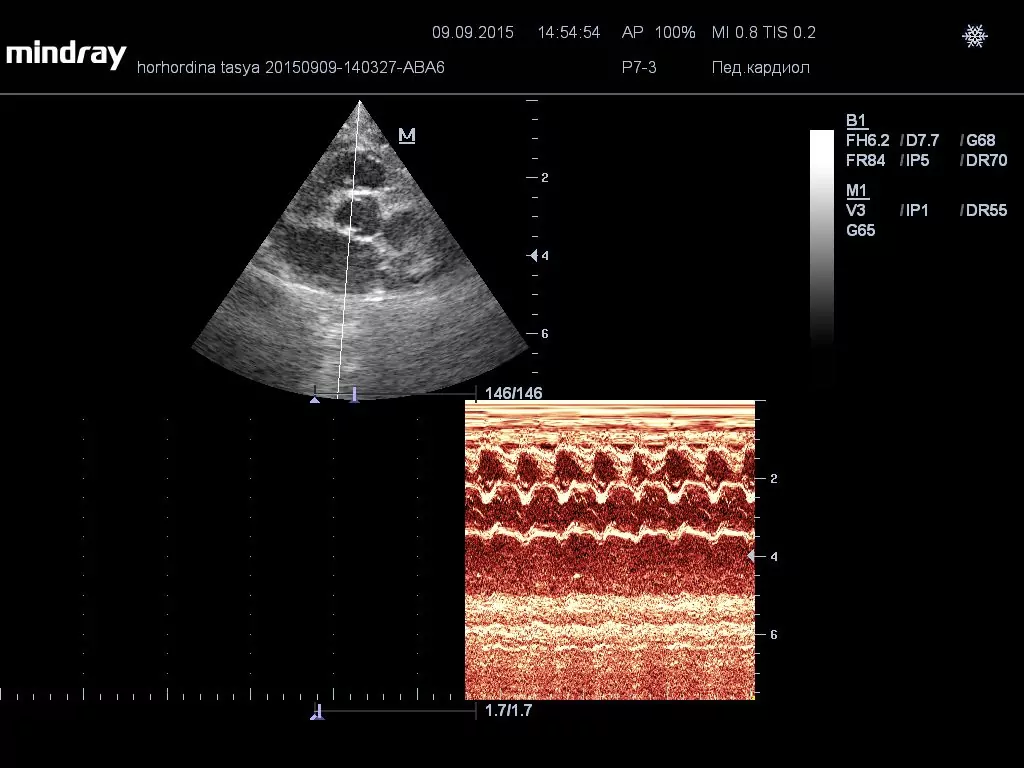

Диагностика ГКМП проходит с помощью эхокардиографии, этот метод дает наиболее точный диагноз, так как используется технология УЗИ.

Врач кардиолог может наблюдать в режиме реального времени за сердцем и его работой